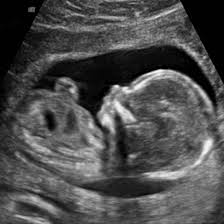

What Does Nt Mean On An Ultrasound - Abdominal Ultrasound Uses Side Effects Procedure Results - This means that you get to watch your child move within the womb.. Ultrasound devices range with frequencies from 20khz to several gigahertz. Nuchal translucency (nt) is a collection of fluid under the skin at the back of your baby's neck. Nuchal translucency (nt) measurement nuchal translucensy (nt) is the clear space in the tissue of your developing baby's neck. This means that you get to watch your child move within the womb. A special ultrasound, called a nuchal translucency screening, measures the back of the baby's neck.

Normally she does it with transabdominal approach. The ultrasound nt scan or nuchal translucency scan is an ultrasound to measure the amount of fluid that has been collected in the back of the neck of the fetus. At times, the nuchal translucency test may add on ultrasound markers, such as measuring a baby's. It is same as normal sound in its physical properties, but humans cannot hear it. Much like the 3d ultrasound, a 4d ultrasound is typically used as a keepsake.

The ultrasound itself will take about 20 minutes to perform. This test measures the size of the clear tissue, called the nuchal translucency, at the back of your. It's often used during pregnancy to check the health of an unborn baby. The nuchal folds are on the back of the fetus's neck, and measuring the thickness of the nuchal folds—an indicator of how much fluid there is inside the folds—can provide information on possible issues with the fetus, including. When the nt is greater than 3.5 mm, there is a 1 in 5 chance of a chromosome abnormality such as turner or down syndrome, or trisomy 18. A look at what your scans will involve. The nuchal translucency screening, or nt, is a prenatal ultrasound test that can help to determine the fetus's likelihood of having down syndrome or some other chromosome abnormality. Before you arrive for your appointment we strongly encourage you to decide which screening test you would like to use to assess the results of your ultrasound.

Among the many terms you will learn and become familiar with is a nuchal scan. Or when your baby measures between 45mm and 84mm, crown to rump. At times, the nuchal translucency test may add on ultrasound markers, such as measuring a baby's. Normally she does it with transabdominal approach. Nuchal translucency (nt) normal range pregnancy is a time when people tend to learn a lot of new terminology. First trimester screening includes an ultrasound exam to measure the size of the clear space in the tissue at the back of a baby's neck (nuchal translucency). This page explains what the acronym nt means. Nuchal translucency (nt) measures an area of fluid at the back of a baby's neck. A nuchal translucency (nt) ultrasound measures the fluid at the back of a baby's neck between 11 and 14 weeks of pregnancy. Nuchal translucency ultrasound alone can also provide this risk assessment, but it is not as accurate as combined first trimester screening. The person performing the nt scan may also ask you to drink a glass of water before you begin. Before you arrive for your appointment we strongly encourage you to decide which screening test you would like to use to assess the results of your ultrasound. In malaysia, the overall rate of incidence for down syndrome is 1 in 800 births.